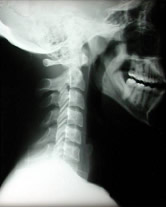

Advanced Orthogonal is the latest development of the upper cervical instrument adjusting techniques. It was developed by Dr. Stan Pierce, Sr. in Saint Petersburg, Florida. It utilizes a table-mounted instrument to deliver a gentle percussion wave adjustment. Before an adjustment can be given, a three-dimensional set of neck x-rays is taken to determine the precise position of the atlas in respect to the skull above and the cervical vertebrae below. Great care is taken to ensure the x-rays are reliable and show the natural posture of the patient. These x-rays are analyzed for the presence of vertebral misalignments with respect to any anatomical aberrancies that might be present.